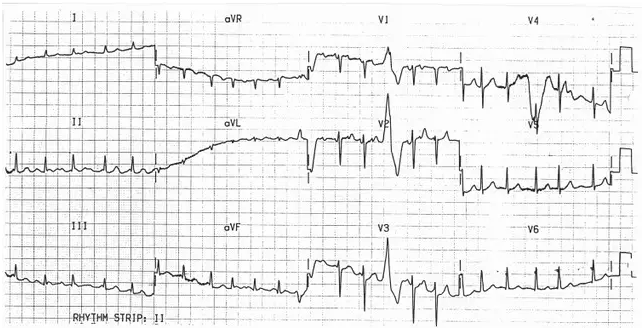

患者为 53 岁女性,儿时曾发生急性风湿热,因「不规则的窄 QRS 波心动过速」而至门诊就诊(图 1)。心前区触诊可扪及明显的左右心室搏动,且有明显的二尖瓣反流杂音。另外还发现,颈静脉怒张、外周水肿和肺部湿罗音,提示充血性心衰。患者拒绝住院,暂且以地高辛和利尿剂治疗。三天后,患者至门诊复诊,发现 ECG 发生变化(图 2)。

图 1 初次入院时 ECG

第一张 ECG 显示房颤并快速心室反应,V1 和 V2 导联可见明显心房去极化,心率高达 300 bpm,提示至少 ECG 检查期间发生过房扑合并变化的房室传导阻滞。除了 V1-V3 导联上可见一个预激的宽 QRS 波,其他 QRS 波都比较窄,因为心室去极化仅仅是单一地贯穿整个房室结、希氏束和其他束支。